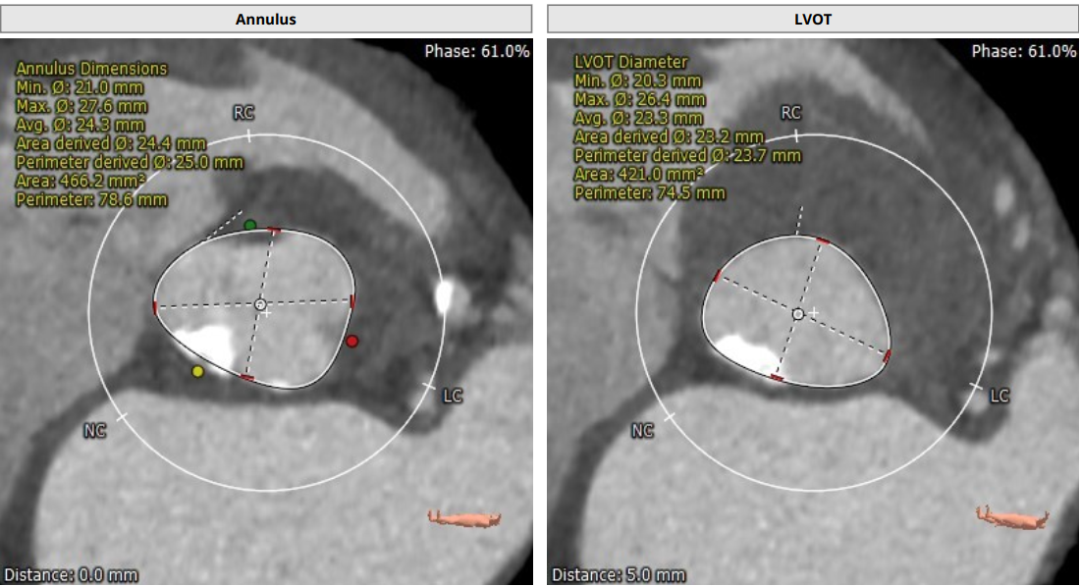

超声心动图显示,主动脉最大流速482cm/s,最大压差93mmHg,平均压差50mmHg,LVEF65%。CT显示主动脉瓣为TYPE2型二叶瓣,严重钙化,右无、左无可见粘连伴钙化,瓣环平面可见钙化,钙化延伸至流出道及二尖瓣前叶根部,左冠高度约12mm,瓣叶长度14.9mm,存在一定左冠风险,法式窦平均直径33.7mm,STJ高度约21.8mm、直径约30.2mm。

主动脉弓部走行较平缓,弓顶部可见少许钙化,主动脉弓部三根毛开口未见明显狭窄征象、未见发育变异,胸主动脉、腹主动脉走行较平直、腹主动脉多发严重钙化斑块,管腔未见明显狭窄,双侧髂动脉-股动脉走形迂曲,双侧髂动脉多发严重钙化斑块,部分呈半环形、马蹄形分布,右侧股动脉可尝试做为主入路,左股动脉作为脑保护入路。虚拟瓣环直径25mm,左室流出道平均直径23.3mm,拟植入VenusA Plus 23/26号的瓣膜。术中balloon sizing确认瓣膜型号,同时确认冠脉风险。